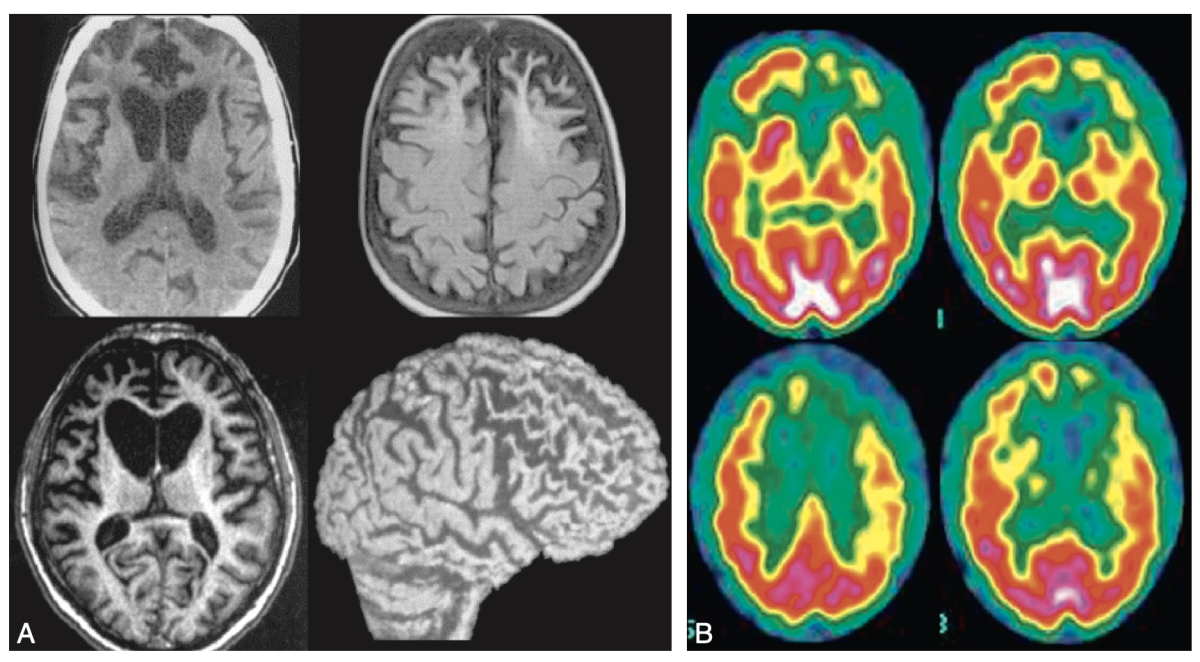

c. Arguments positifs d’imagerie métabolique

La scintigraphie de perfusion peut mettre en évidence une hypoperfusion des régions corticales associatives et temporales internes. La tomographie par émission de positrons (TEP) détermine le métabolisme cérébral par un radiomarquage fluoré du déoxyglucose (TEP-FDG), qui peut mettre en évidence un hypométabolisme de ces mêmes régions.

Il existe plusieurs formes cliniques. La forme la plus fréquente est la forme comporte- mentale (due principalement à une dégénérescence des zones ventrales des lobes frontaux), mais il existe aussi des formes plus rares débutant par des troubles du langage constituant une aphasie primaire progressive.- L'IRM cérébrale peut montrer une atrophie du cortex frontal et du tissu sous-cortical (entraînant un aspect «ballonisé» des cornes ventriculaires frontales), tandis que la scintigraphie de perfusion et le PET-scan métabolique montrent une hypoperfusion ou un hypométabolisme des régions frontales et temporales (figure 18.6).

Fig. 18.6.

Démence frontotemporale. A. IRM. B. Scintigraphie de perfusion.

L'IRM et la scintigraphie de perfusion montrent une atrophie/hypoperfusion dans les régions frontales, temporales antérieures et cingulaires. Noter, en IRM, l'aspect ballonisé des cornes frontales des ventricules latéraux.

(Source : CEN, 2019.)